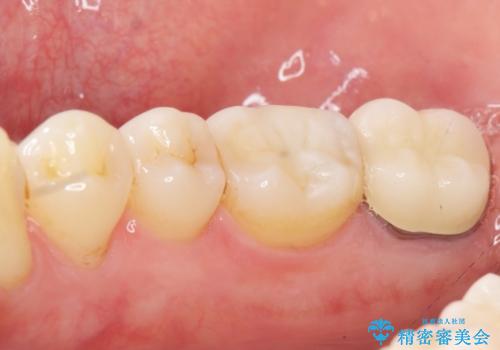

隣の歯(右下6)はセラミックインレーで修復しました。

歯周外科処置(右下7遠心の骨整形及びディスタルウェッジ)により、深部に及ぶう蝕を除去するとともに歯肉縁上の健全歯質を獲得でき、適合の良い被せ物を作製することができました。

不適合な銀の詰め物とう蝕の除去により奥歯の違和感がなくなり、セラミック治療により機能性・審美性が向上し、患者様に喜んで頂けました。

被せ物の種類:右下6 e-max press セラミックインレー

右下7 メタルボンドクラウン エコノミー